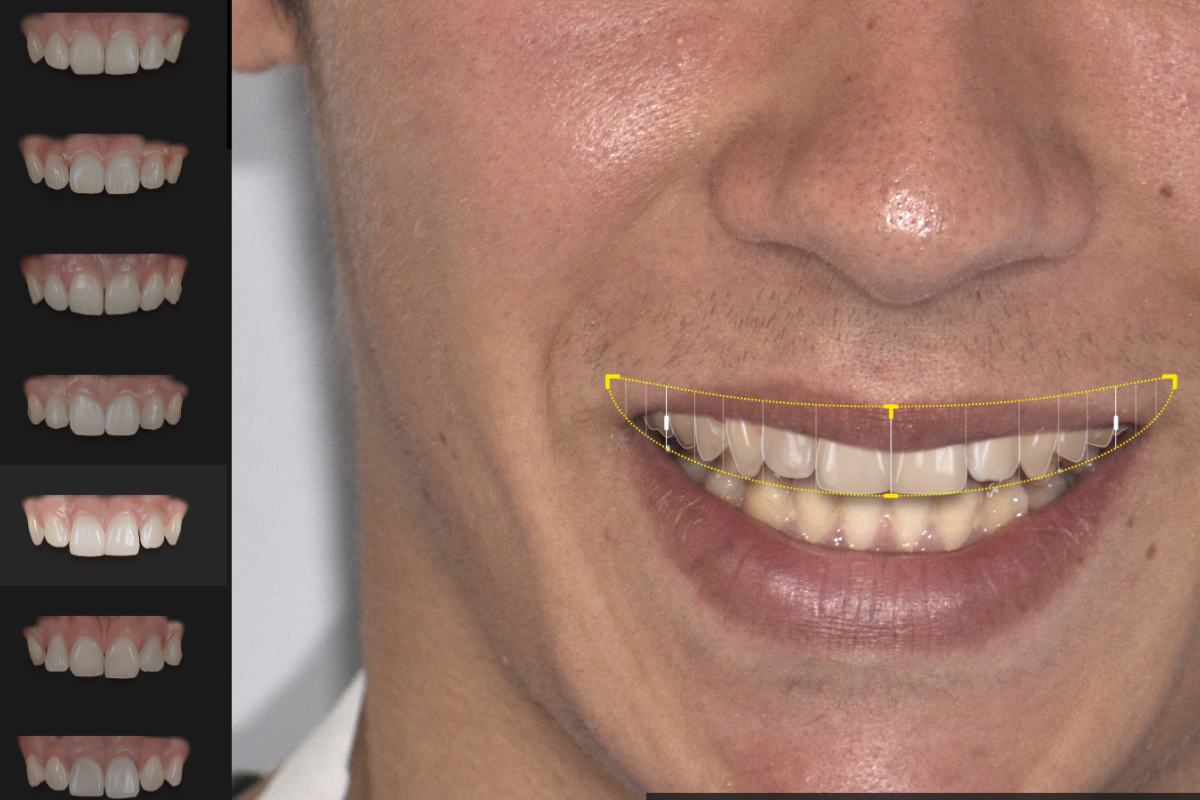

Projet esthétique virtuel

L’analyse esthétique virtuelle permet de visualiser le résultat potentiel de votre traitement avant même de commencer. Grâce à des logiciels spécialisés, nous étudions l’harmonie du sourire, la position des dents et les proportions du visage afin de concevoir un plan de traitement sur mesure. Cette technologie facilite la communication entre le patient et le dentiste et permet de définir ensemble un sourire naturel et équilibré.